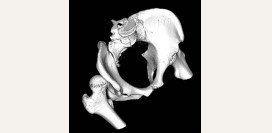

Тазобедренный сустав образован вертлужной впадиной таза и головкой бедренной кости.

Вертлужная впадина имеет вид полукруглой чаши. По ее краю проходит хрящ в виде ободка, который дополняет ее и ограничивает движения в суставе. Таким образом, сустав составляет 2/3 шара. Хрящевой ободок, который дополняет вертлужную падину, покрыт изнутри суставным хрящом. Сама костная впадина заполнена жировой тканью.

Головка бедренной кости также покрыта суставным хрящом. Она имеет шарообразную форму и соединяется с телом кости при помощи шейки бедра, имеющей небольшую толщину.

Суставная капсула прикрепляется по краю вертлужной впадины, а на бедре покрывает головку и шейку.

Внутри сустава находится связка. Она начинается от самой верхушки головки бедра и присоединяется к краю суставной впадины.

Она называется связкой головки бедра и выполняет две функции:

• амортизация нагрузок на бедренную кость во время ходьбы, бега, прыжков травм;

• в ней проходят сосуды, которые питают головку бедренной кости.